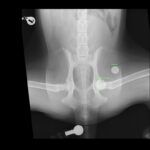

若齢のゴールデン・レトリーバーの股関節形成不全(CHD)に対し、人工股関節全置換術(THR)を実施しました。術前のエックス線では、両側に顕著な股関節亜脱臼を認めましたが、重度の変形性関節症は認められていません。亜脱臼が顕著であることから関節温存のための3Dhip/DPO/TPOは不適応と判断しました。

手術前には vPOP Pro を用いて詳細な術前シミュレーションを行いました。

今回、選択したインプラント

• Acetabular Cup:26.5 mm

• Femoral Stem:Size M/Neck Short/Head19mm